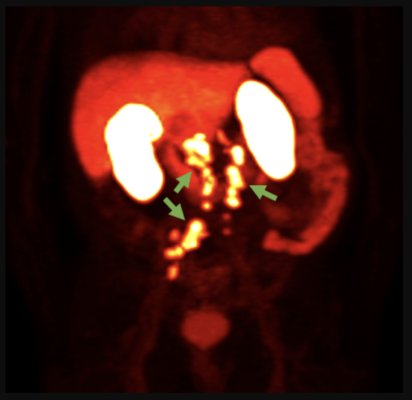

18F-rhPSMA-7.3 PET image showing prostate cancer spread beyond the prostate region (Photo courtesy of Blue Earth Diagnostics)